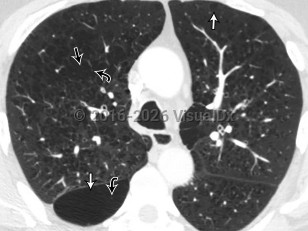

Chronic obstructive pulmonary disease (COPD) is a preventable and treatable condition with both pulmonary and extrapulmonary effects. Despite this, it is the third leading cause of death worldwide. COPD is characterized by chronic airflow obstruction that is not fully reversible. The disease is usually progressive and due to an abnormal inflammatory response in the lungs. Extrapulmonary manifestations include systemic inflammation, weight loss / nutritional deficiency, anemia, skeletal muscle dysfunction, and an increased risk for cardiovascular comorbidities.

Risk factors for the development of COPD include cigarette smoke exposure (primary or secondary) and occupational exposures (organic and inorganic dusts, chemical fumes, and smoke) as well as biomass fuel smoke exposure (from combustion of fuel developed from plant or animal materials, eg, wood, crops, animal waste, and some municipal solid waste) in the developed setting. Patients with alpha-1 antitrypsin deficiency, an inherited disorder, are at increased risk for developing COPD, including at a younger age.

COPD due to cigarette smoke exposure leads to more severe emphysema and more rapid decline in lung function compared with COPD from biomass exposure. The latter presents with distinctive airway wall thickening and sees lung function improve from the use of bronchodilators. The number of symptoms, exacerbations, and hospitalizations is higher in patients with asthma leading to COPD compared with patients with smoking-associated COPD, although, paradoxically, the asthma-associated mortality rate is lower.